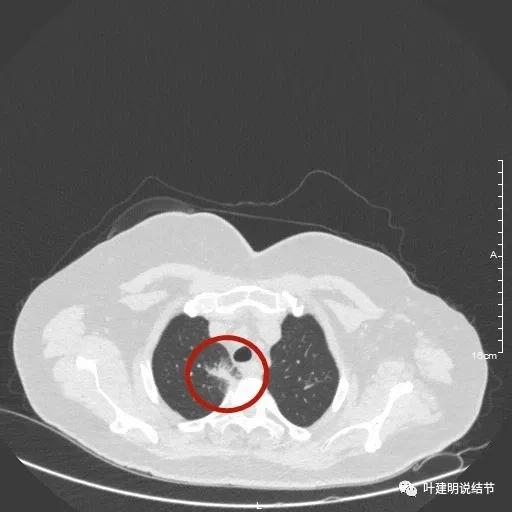

這種多發磨玻璃病灶,存在三年了,抗炎治療無效,會是什麼疾病呢?第一印象是內科什麼疾病的肺部表現。但臨床上沒有其他的症狀,感覺用其他內科疾病來解釋不太符合。因為我們經常總結碰到的病例,我腦子中突然想到一種疾病,在之前分析過的。在省級醫院多堂會診都沒有診斷出來,找我就診諮詢時,我考慮惡性建議起區域性切除治療。病理居然是淋巴瘤,這是我術前沒有料到的,但經過回顧分析,對這一型別的淋巴瘤有了一定的瞭解。今天這個病例的影像表現與前面淋巴瘤的這個病例非常像。我們來看看被確診為淋巴瘤的這個病例影像是怎樣的:

大家覺得怎麼樣?經過影象特徵的對比,我感覺是同一類毛病的可能性非常大!我建議她到血液科就診諮詢,或者必要時做穿刺活檢以明確。